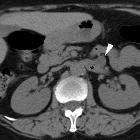

Asymptomatic

left renal vein aneurysm with thrombosis. Multiplanar reformatted images (b..d) from portal venous phase acquisition depicted the lesion (arrowheads) as a saccular outpouching of the left renal vein (*), with internal nonenhancing tissue (thin arrows) representing intraluminal thrombus.